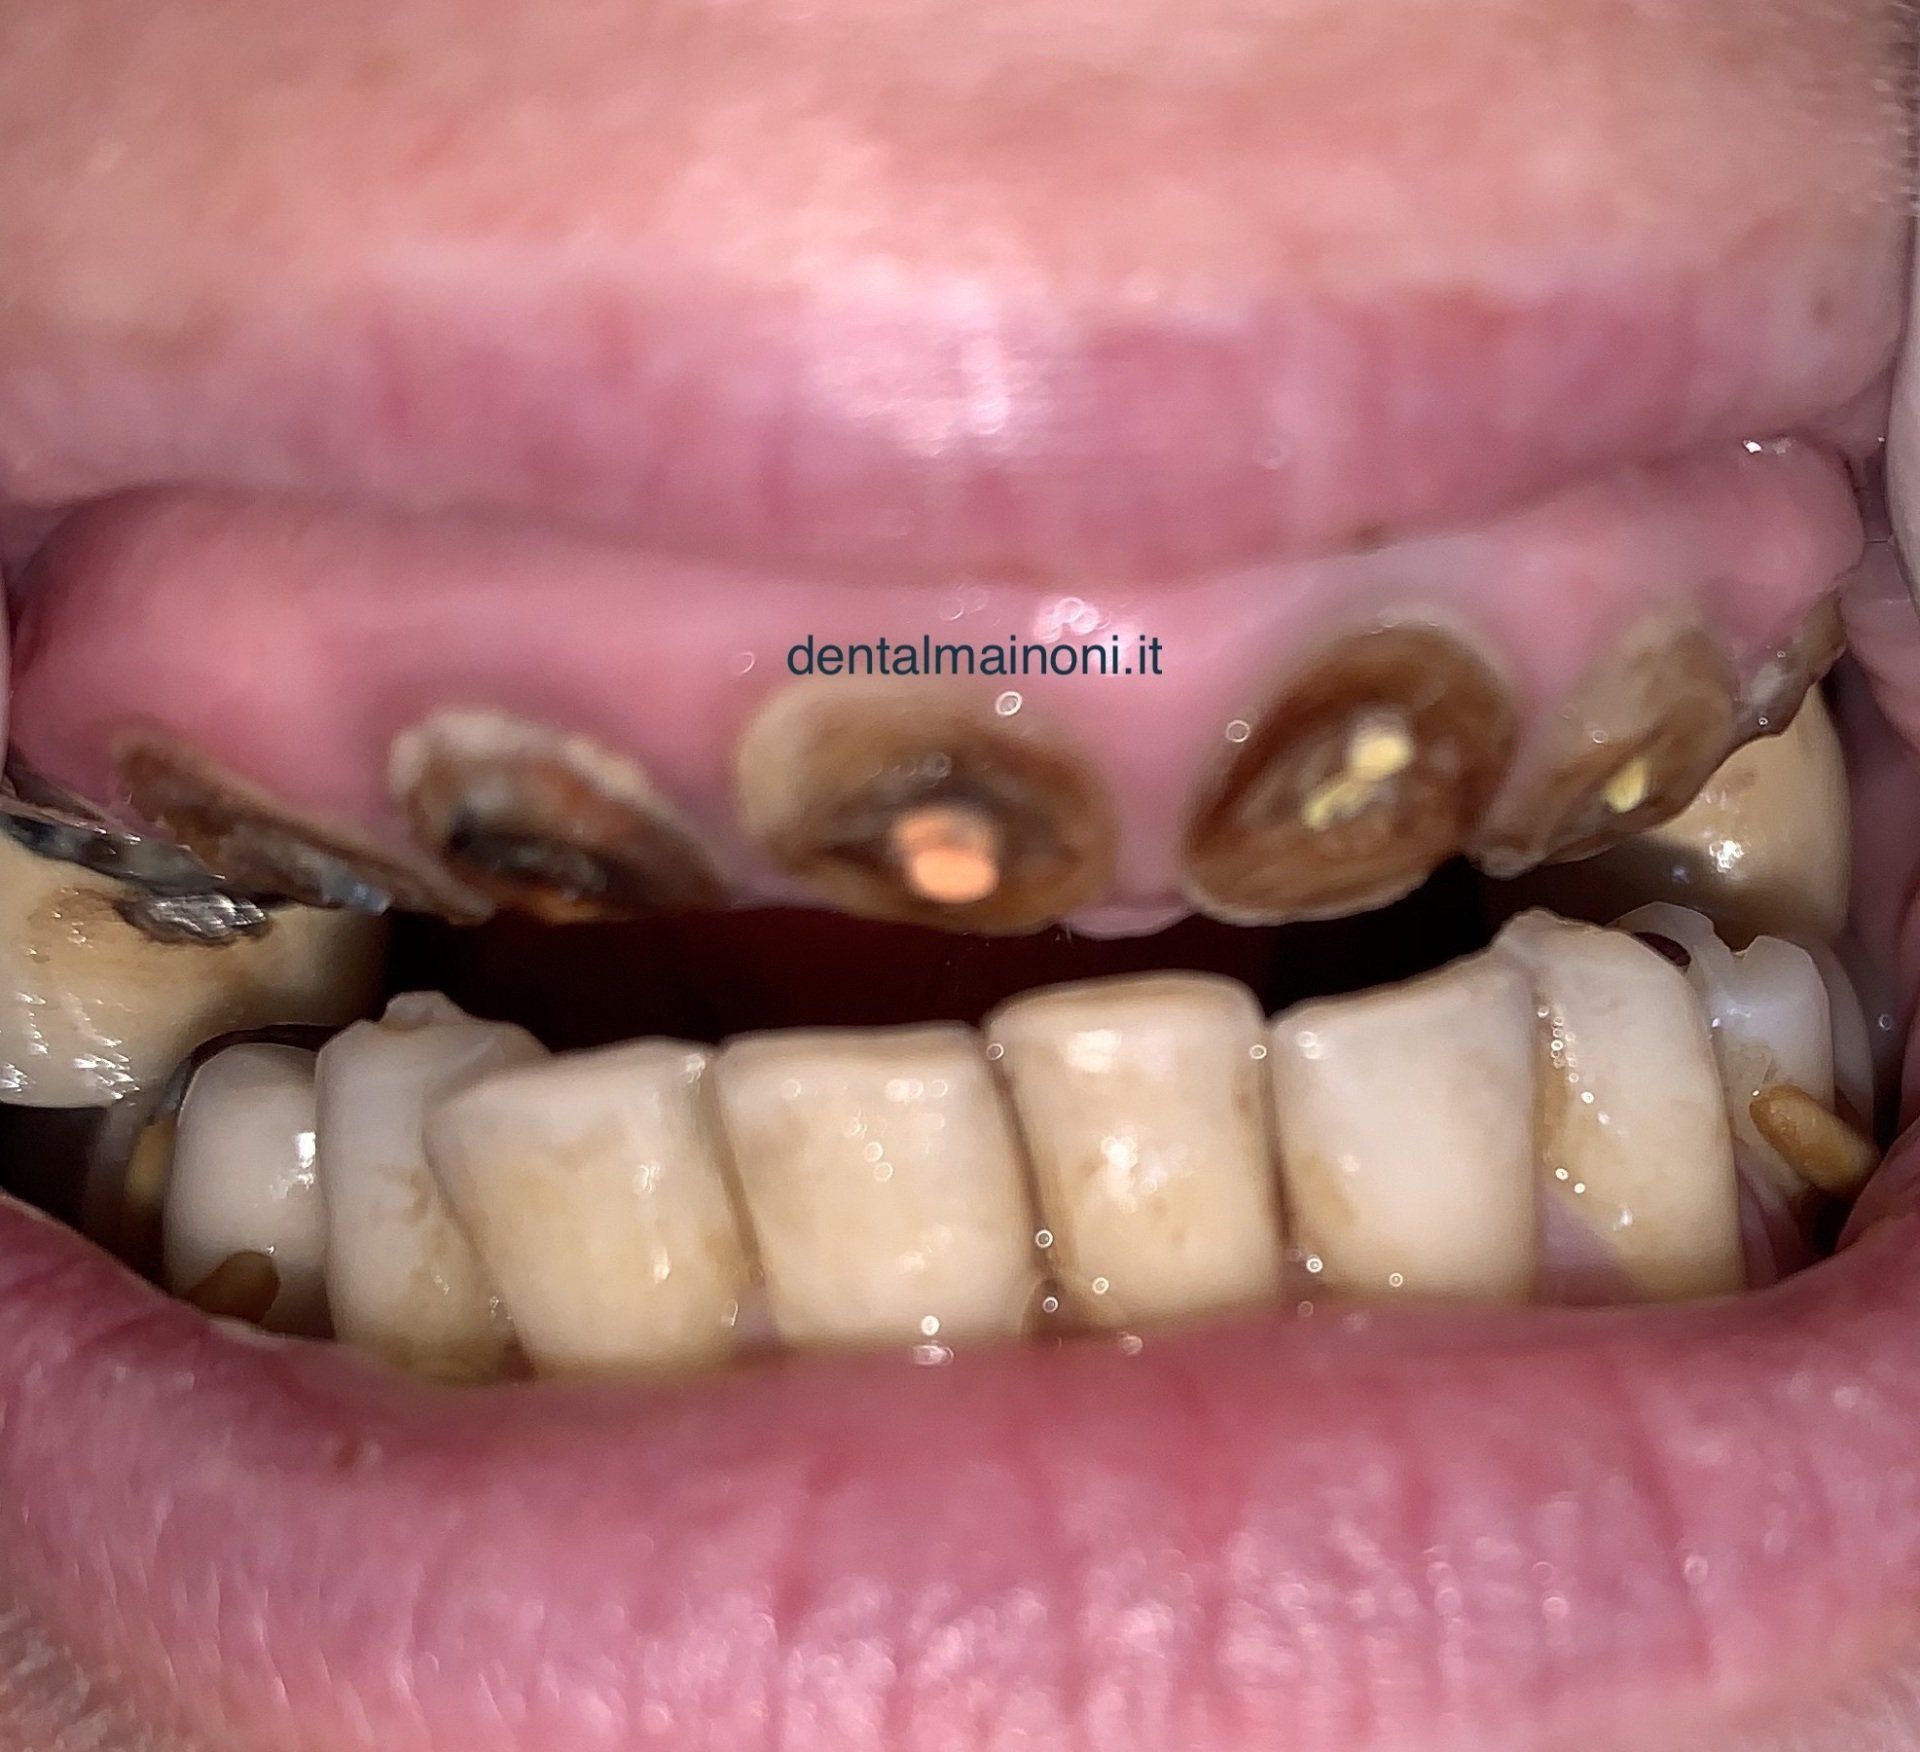

UN'EMERGENZA DENTALE / FOTO 1

ButtonUna paziente si presenta alla nostra osservazione dopo un grave trauma funzionale ed estetetico per un incidente stradale.